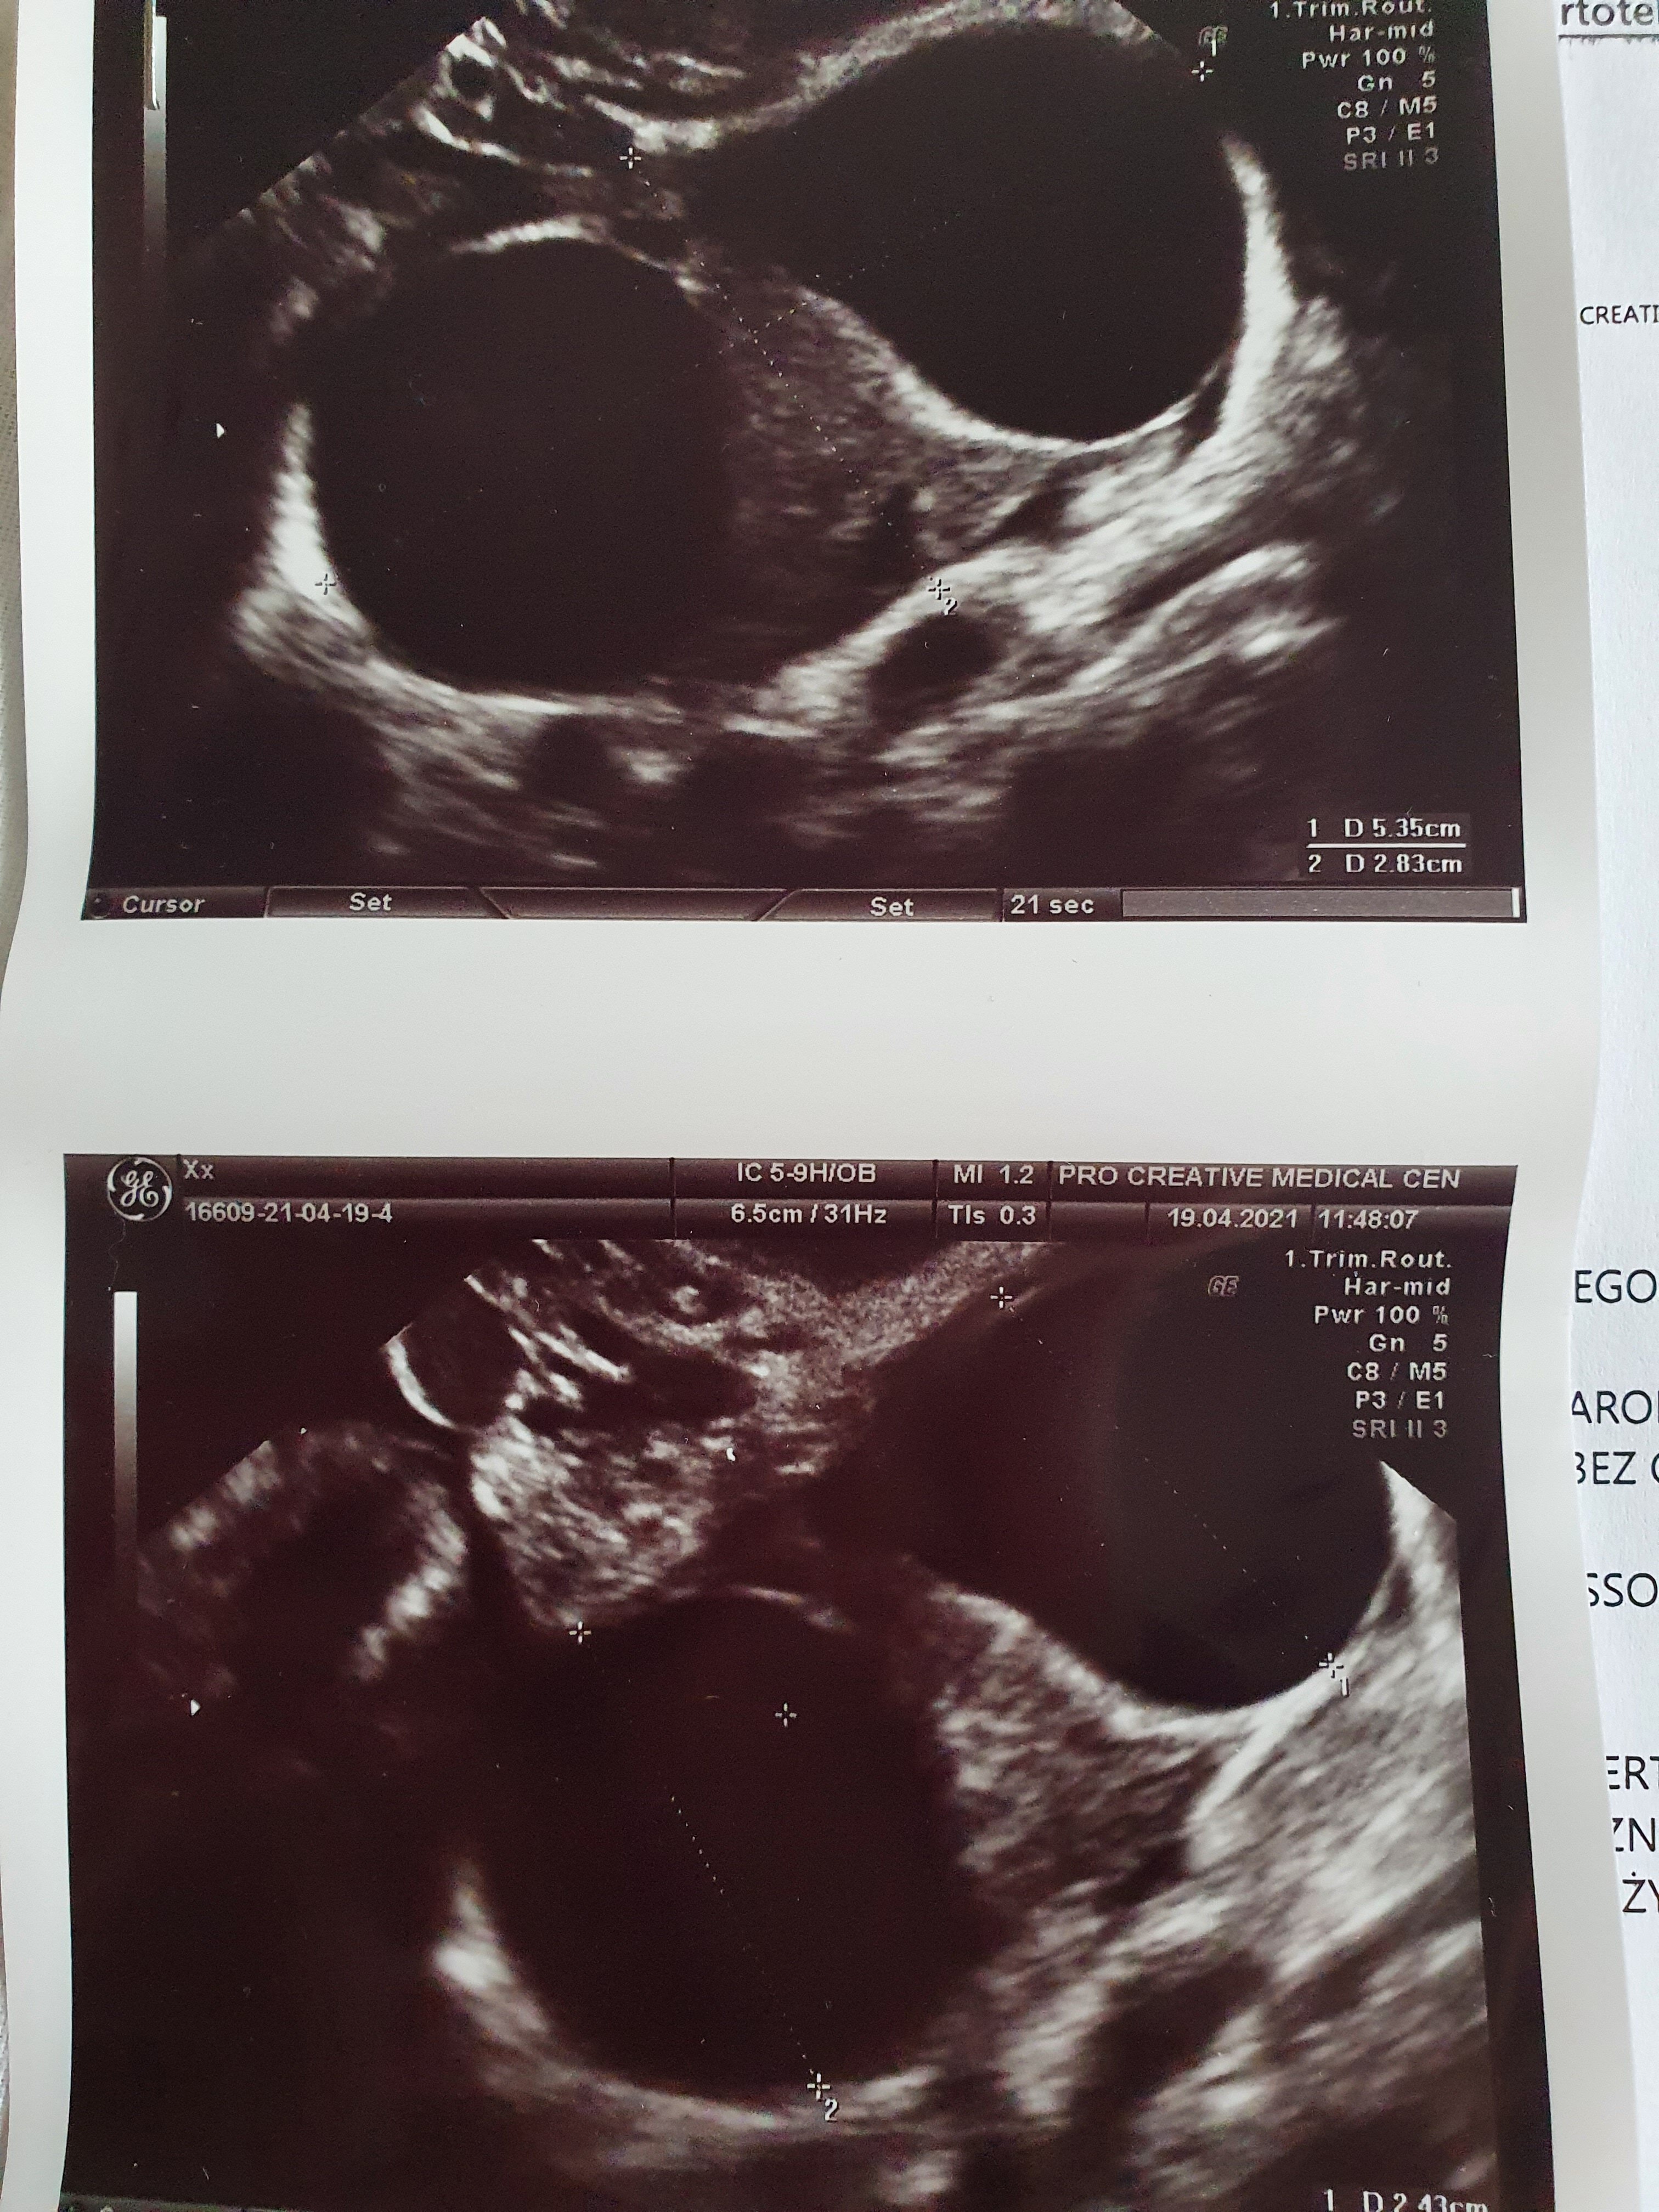

Wróciłam od lekarza, do końca normalnie nie jest. Wg pomiaru 4+6, pęcherzyk jest w macicy, na razie bez zarodka i ciałka żółtego. Za to mam dwie wielkie torbiele, jedna ma wyrzuty krwi, a druga może być pozamaciczną co muszę kontrolować. W razie plamień i silniejszego bólu jajnika mam jechać do szpitala, za tydzień kolejna kontrola, jeśli cysty będą się powiększały położy mnie do szpitala.

Załączniki

• 20210419_125755.jpg

20210419_125755.jpg

1,7 MB · Wyświetleń: 117

• 20210419_130152.jpg

20210419_130152.jpg

2 MB · Wyświetleń: 108

• 20210419_125643.jpg

20210419_125643.jpg

2 MB · Wyświetleń: 102